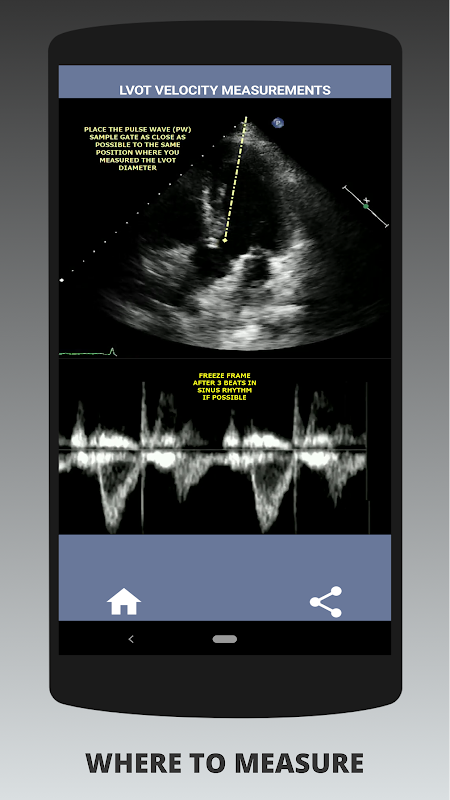

Pada pendapat saya, sekiranya seseorang yang ditemubual dapat menunjukkan keahlian ini, seseorang itu mempunyai kelebihan besar berbanding pemohon lain yang lemah dalam bidang ini (itu adalah logik kerana biasanya terdapat banyak kes stenosis aorta). Sekiranya anda melamar posisi sonographer jantung, seseorang yang hanya perlu menyegarkan kemahirannya, atau pelajar echo, maka aplikasi ini direka oleh anda oleh sonographer jantung yang sedang berlatih. Ringkas dan pendek, tepat dengan banyak video ilustrasi yang menunjukkan dengan tepat di mana untuk mengukur (mis. Diameter LVOT) dan cara mengukur mengikut garis panduan ASE / ICAEL yang diterbitkan.